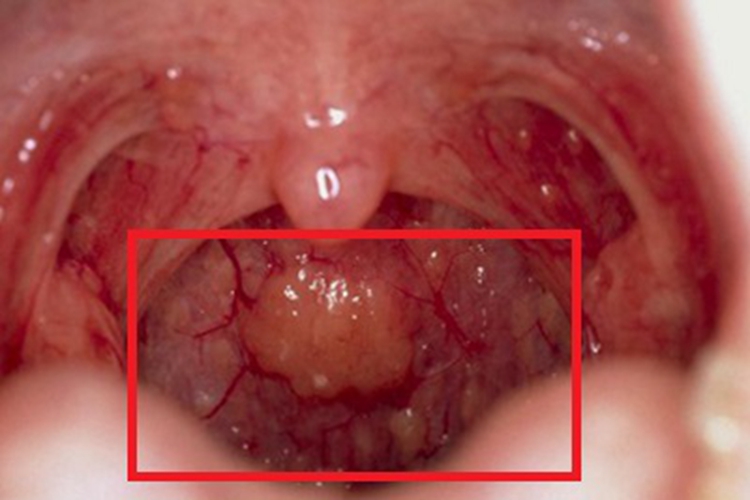

慢性咽炎可导致咽喉部位出现大小不一、数量不等的疙瘩,表面呈淡红色,形状并不规则,凸起于黏膜表面,并有充血、红肿。患者可出现咽部异物感、痒感、干燥感等不适。

慢性咽炎患者要坚持户外活动,戒烟酒,保持室内空气清新,积极治疗鼻炎、气管支气管炎等疾病。患者可遵医嘱使用复方硼砂含漱液、复方氯己定含漱液含漱,亦可含服复方草珊瑚含片、薄荷喉片等。若存在淋巴滤泡增生,可用激光、低温等离子治疗,亦可用硝酸银、冷冻或电凝固法治疗。